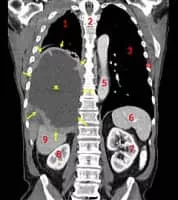

Oncology photograph

Oncology is a branch of medicine that deals with the prevention, diagnosis, and treatment of cancer. A medical professional who practices oncology is an oncologist. The name's etymological origin is the Greek word ὄγκος, meaning "tumor", "volume" or "mass" and the word λόγος, meaning "study".